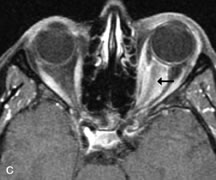

Lymphomas have MRI characteristics similar to those of inflammatory lesions in that they are hypointense to fat and isointense to muscle on T1-weighted images (Fig. 22). They may appear hyperintense to fat on T2-weighted images, perhaps owing to less fibrosis than that seen in orbital inflammatory pseudotumor, although this is not a consistent finding.31,50,66 Lymphoid tumors typically enhance moderately after contrast injection. Unfortunately, studies have shown that tumor density and homogeneity are similar between inflammatory and malignant orbital infiltrates, and MRI cannot differentiate these lesions.72,73

Fig. 22. A and B. T1- and (C) T2-weighted MR scans demonstrate a poorly defined multicompartmental mass enveloping the lateral rectus, superior rectus, and levator palpebrac superioris muscles. The lesion is isointense to brain on T1- and T2-weighted scans, as is typical for highly cellular neoplasms. D. Postcontrast fat-suppressed T1-weighted scan demonstrates intense enhancement of the infiltrating intraconal and extraconal tumor.